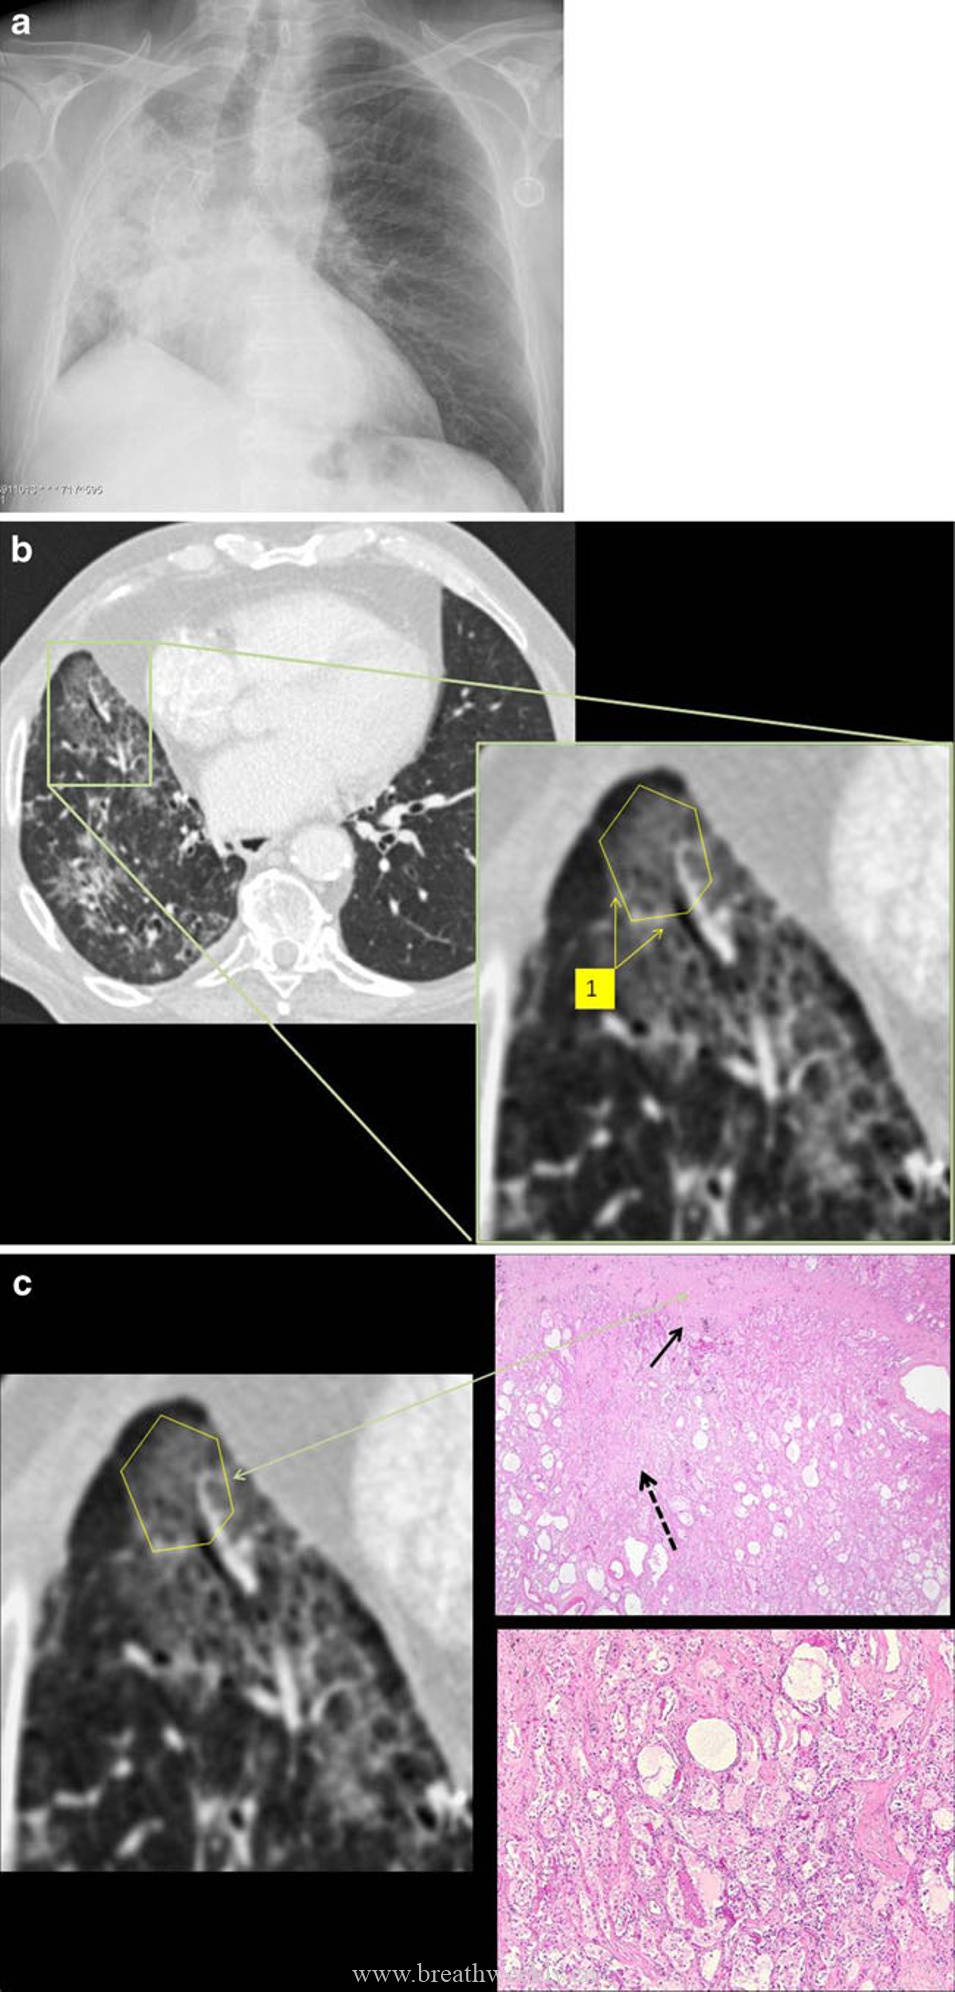

病例1:肺泡蛋白沉积症

临床资料:46岁男性,进行性呼吸困难1周,咳嗽,晨起咳白色粘痰。

影像表现:胸片显示以肺部中央为主的网状影,双肺中央密度增高。CT显示双肺斑片状铺路石征。

病理对照:肺泡内嗜酸性无定形物质,PAS染色阳性,对应表面活性物质缺乏。线状影对应腺泡边缘气腔内物质沉积(腺泡周围型)。

肺泡蛋白沉积症和外源性脂质性肺炎是气腔疾病。在肺泡蛋白沉积症中,气腔被磷脂蛋白样物质填充。CT上肺泡填充导致磨玻璃影,当邻近小叶间隔和肺泡壁的气腔被填充时,形成腺泡周围型。